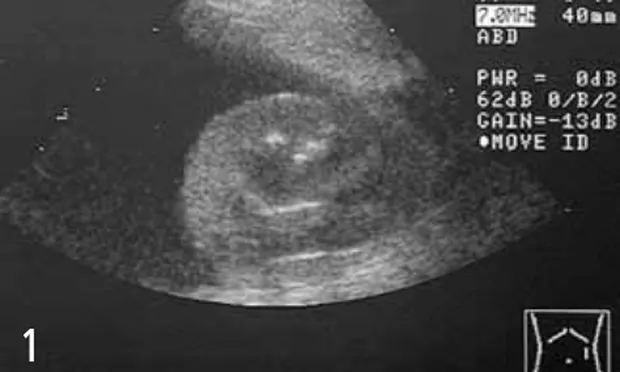

Transverse ultrasonographic image of normal-appearing left kidney surrounded by anechoic ascites. Hyperechoic tissue in the near field is body wall and musculature.

Abdominal radiographs may not be helpful. In most animals with clinical signs consistent with gastrointestinal disease, abdominal radiographs are invaluable and should be part of the diagnostic workup. Radiographs may reveal a variety of abnormalities, such as foreign objects, intussusception, masses, and gastric malpositioning. However, in cases of animals with ascites, poor abdominal detail will prevent identification of abdominal structures, so abdominal ultrasonography is more helpful to rule out masses (Figure 1).